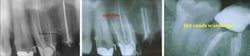

To enhance my ability to visualize the canal, I often superimpose two intraoral films taken at slightly different angles to help visualize the canals for access, thorough instrumentation, and complete obturation. For example, I might superimpose two images of a maxillary molar (see figures 5 and 6, below) clearly delineating the buccal and palatal canals to help visualize the tooth's likely additional mesiobuccal canal (see figure 7, below).